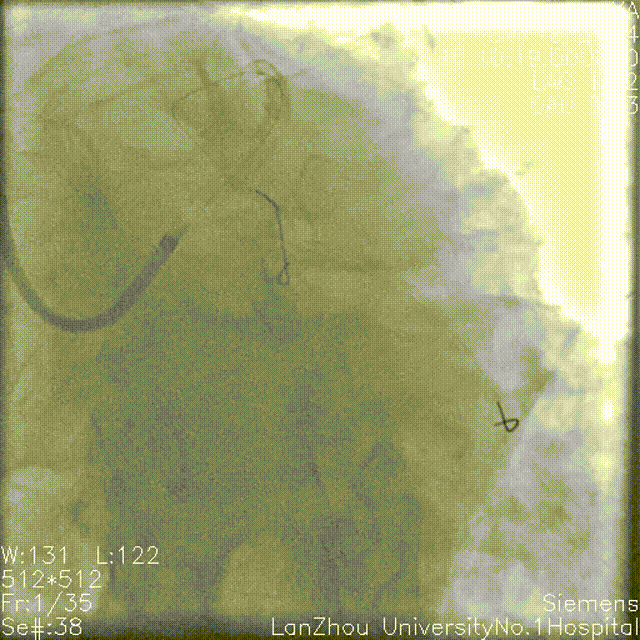

头位造影:

LM较短,末端可见重度狭窄,前降支近中段全程弥漫性狭窄伴钙化;

回旋支次全闭,可见钙化影。

右肩造影:

前降支近中段全程弥漫性狭窄伴环形钙化,最重处95%狭窄;

对角支开口狭窄不重,角度不大,可能不需要导丝保护。

蜘蛛位造影:

左主干开口、体部未见明显狭窄;

第一对角支开口重度狭窄;

回旋支次全闭,开口、近端、中段重度狭窄,可见环形钙化。